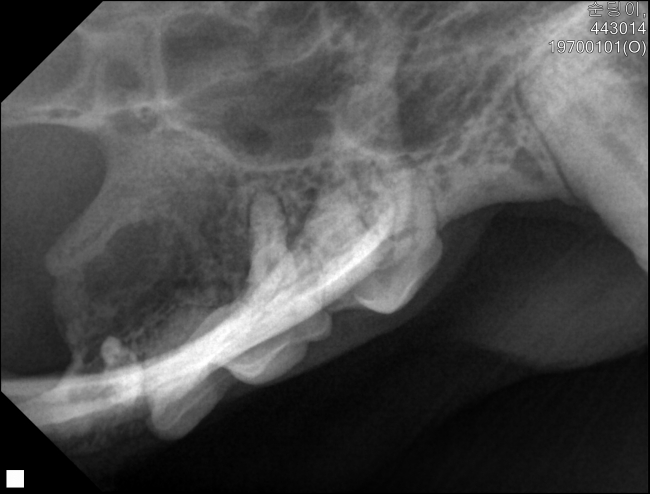

치료중 대상묘